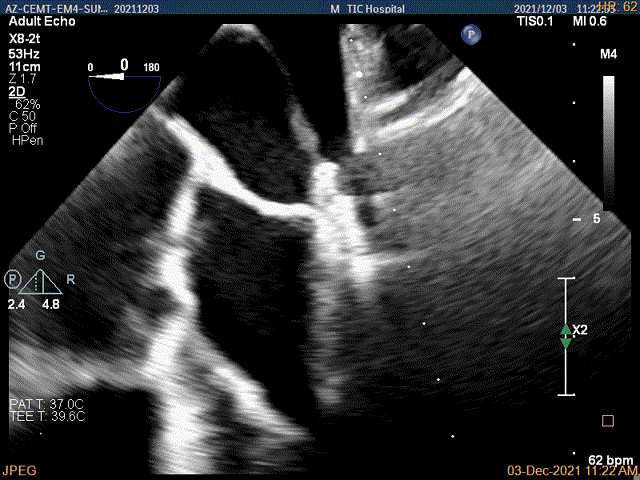

2D视图下trajectory

X-plane:下夹子尝试先捕获1区脱垂瓣叶

夹子关闭过程中,Color提示1区反流逐渐减少